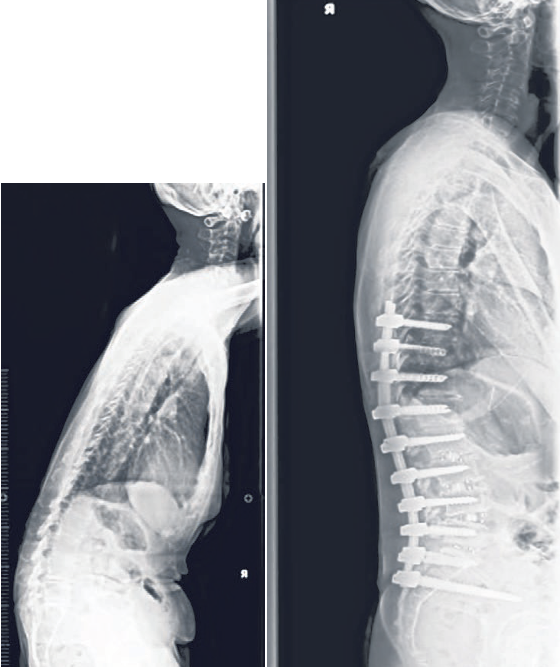

图为一名脊柱后凸畸 形病患术前(左)和 术后(右)的X光照, 通过放置金属棒和螺 钉等方法帮助固定和 支撑脊柱。 (陈笃生医院提供)

手术治疗的目的是纠正脊椎后凸 畸形,让患者站立时可以保持挺直。 手术类型因人而异。脊柱后凸畸形的 常见手术类型如脊柱固定和融合,可 包括放置金属棒和螺钉来改善脊柱对 齐的情况。